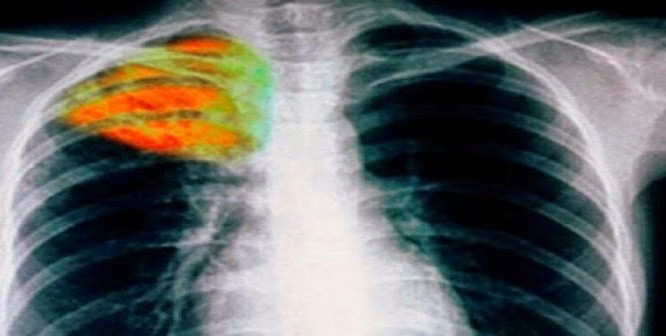

Η φυματίωση είναι νόσημα που προκαλείται από ένα μικρόβιο που λέγεται μυκοβακτηρίδιο της φυματίωσης και σπανιότερα από άλλους τύπους μυκοβακτηριδίων. Το μυκοβακτηρίδιο της φυματίωσης μπορεί να προσβάλει οποιοδήποτε όργανο του σώματος, αλλά συνήθως προσβάλλει τους πνεύμονες.